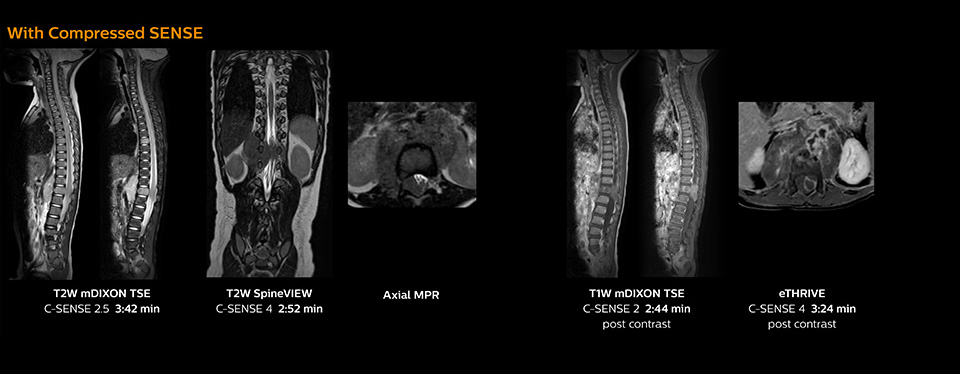

Boosting diagnostic confidence with multiple contrasts, multiple orientations in spine MRI

“Previously with SENSE, our 2D mDIXON TSE scans required relatively long scan times. But now, with Compressed SENSE, we have reduced these scan times while maintaining a high SNR, because the Compressed SENSE technology helps reduce noise,” says Dr. Koyama. “Because the faster scanning with Compressed SENSE saves us time, we can sometimes add a sequence to obtain high quality spine images in the same time slot for confident diagnoses. And in cervical spine exams, a 2D sequence is sometimes replaced by a 3D protocol, which provides us more information as it can be reformatted in different orientations. Compressed SENSE allows us to easily add this 3D sequence in the timeslot,” says Fukushima “Incorporating Compressed SENSE in common spine sequences, such as mDIXON, 3D SpineVIEW and eTHRIVE, can substantially reduce the scanning time of these sequences, while maintaining adequate spatial resolution, resulting in high quality, multiple contrasts, multiple orientations,” says Dr. Koyama. “In addition, fast sequences generally make it easier for patients to stay motionless throughout the scans, so it also helps us in that way.”

The KCH team has already changed most of their Ingenia 1.5T spine ExamCards by incorporating Compressed SENSE into their 2D TSE, mDIXON TSE, FFE, and 3D sequences.

Pediatric spine with neuroblastoma

This 6-year-old patient with neuroblastoma underwent MRI on the Ingenia 1.5T. Compressed SENSE was used to reduce scan time while maintaining the high resolution for 2D mDIXON, 3D SpineVIEW and e-THRIVE in this case. The highly detailed images allowed the radiologist to make a quick and confident assessment of the position of the nerve and the tumor. Especially important for a pediatric patient, is that a shorter scan time also allows us to keep the sedation time as short as possible.

As this was one of the first patients scanned with Compressed SENSE, 3D SpineVIEW was acquired with and without Compressed SENSE to allow comparison. Although the Compressed SENSE sequence was significantly faster, the acquired and reconstructed 3D SpineVIEW images show virtually the same image quality.